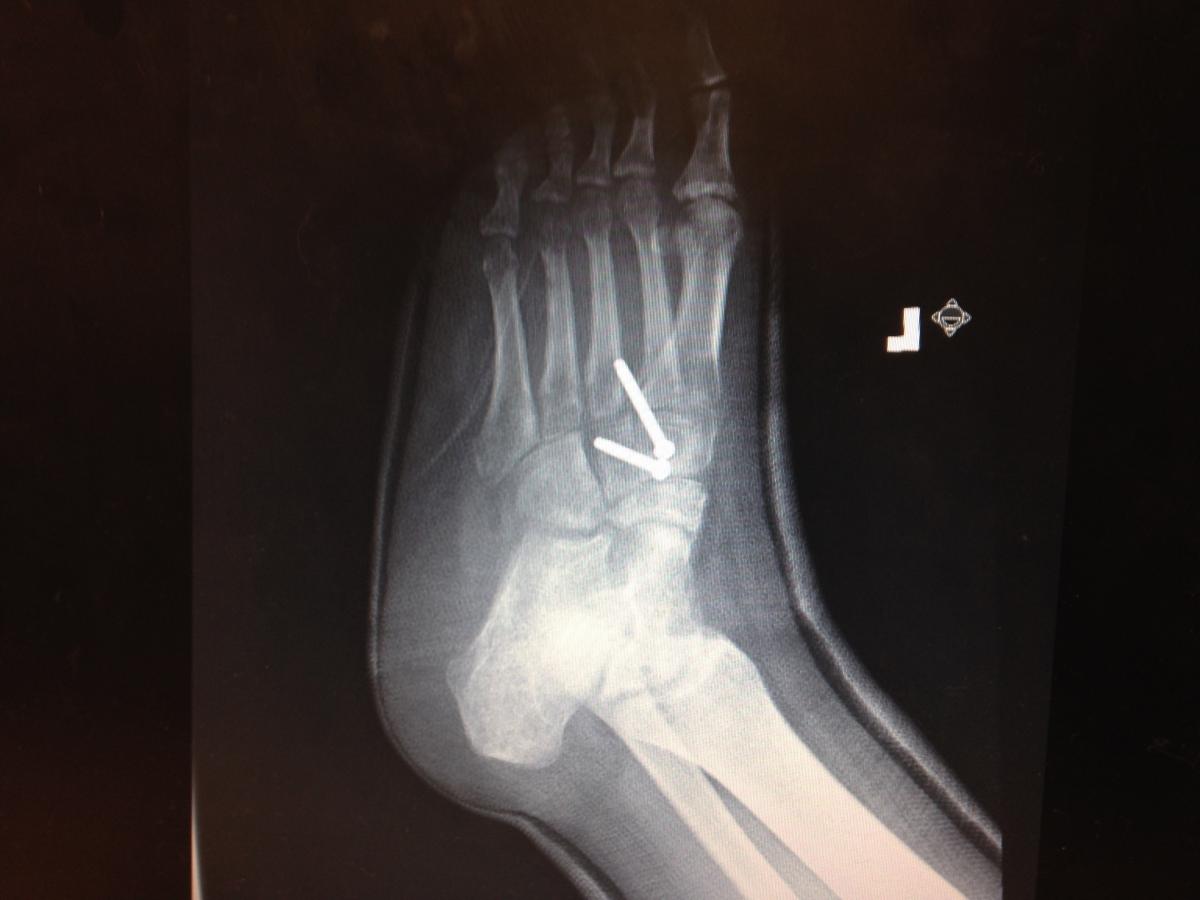

13. The insurance company denied bilateral X-rays when there was no pathology mentioned on the contralateral foot, even when the doctor documented taking a comparison view. In addition, there was no X-ray report for the contralateral foot so the carrier denied it as well. There were instances in which the insurer denied bilateral X-rays because the chief complaint only mentioned a problem with one foot, even though the exam revealed pathology with both.

14. If you have taken one postoperative X-ray, you need to justify a reason to take further X-rays in the chart, especially if the documentation states the patient is doing well and having minimal pain. For example, if you want to check the status of an osteotomy during the post-op time you have to state that in the progress note.

15. There are several instances in which there was not an X-ray report in the chart.